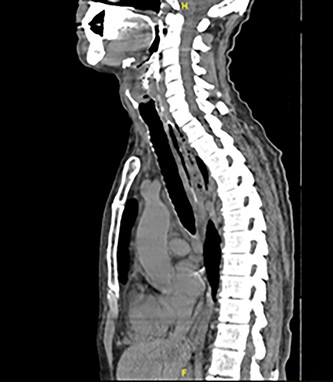

Full blood count, renal function and coagulation profile were within normal limits. C-Reactive protein was mildly raised at 73 mg/l. Neck axial contrast enhanced computer tomography (CT) scan was consistent with significant paraesophageal gas and mediastinitis (Fig. 1). Magnetic resonance imaging (MRI) suggested an enhancing collection from the left parapharyngeal space extending to the mediastinum (Fig. 2). Intravenous Fluconazole was added.

Sagittal plane CT neck and thorax with oral contrast showing significant parapharyngeal gas.